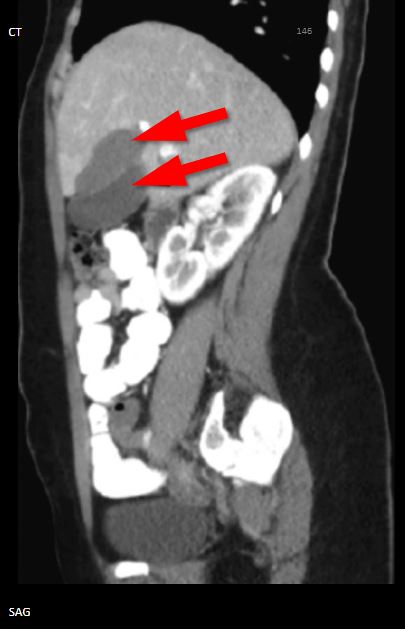

n ultrasound, duplicated gallbladder presents as two discrete adjacent gallbladder lobes as opposed to a single oblong vesicle. Sonographic evaluation of the gallbladder is considered the most helpful and highly sensitive diagnostic tool in assessing gallstones, cholecystitis, and other gallbladder conditions. However, in the setting of the duplicated gallbladder, ultrasonography may not completely differentiate it from other conditions such as Phrygian cap or choledochal cyst. Also, differentiation of the specific type of duplication is typically not possible with ultrasound alone since even with current real-time equipment, the cystic duct is challenging to identify. CT and MRI are more effective imaging techniques to confirm the diagnosis and delineate the classification type of suspected gallbladder duplication